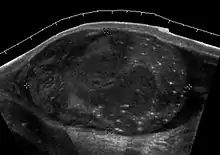

Fig. 26. Testicular torsion of the right testis. Absence of vascular flow and ill-defined hypoechoic lesions are seen in the testis.

The normal testis and epididymis are anchored to the scrotal wall. If there is a lack of development of these attachments, the testis is free to twist on its vascular pedicle. This will result in torsion of the spermatic cord and interruption of testicular blood flow. Testicular torsion occurs most commonly at 12 to 18 years but can occur at any age. Torsion results in swelling and edema of the testis, and as the edema increases, testicular perfusion is further altered. The extent of testicular ischemia depends on the degree of torsion, which ranges from 180° to 720° or greater. The testicular salvage rate depends on the degree of torsion and the duration of ischemia. A nearly 100% salvage rate exists within the first 6 hours after the onset of symptoms; a 70% rate, within 6–12 hours; and a 20% rate, within 12–24 hours. Therefore, testicular torsion is a surgical emergency and the role of ultrasound is to differentiate it from epididymitis as both disease presents with acute testicular pain clinically.

There are two types of testicular torsion: extravaginal and intravaginal. Extravaginal torsion occurs exclusively in newborns. Ultrasound findings include an enlarged heterogeneous testis, ipsilateral hydrocele, thickened scrotal wall and absence of vascular flow in the testis and spermatic cord. The ultrasound findings of intravaginal torsion vary with the duration and the degree of rotation of the spermatic cord. Gray scale ultrasound may appear normal if the torsion just occurs. At 4–6 hours after onset of torsion, enlarged testis with decreased echogenicity is seen. At 24 hours after onset, the testis appears heterogeneous due to vascular congestion, hemorrhage and infarction. As gray scale ultrasound is often normal during early onset of torsion, Doppler sonography is considered essential in early diagnosis of testicular torsion. The absence of testicular flow at color and power Doppler ultrasound is considered diagnostic of ischemia, provided that the scanner is set for detection of slow flow, the sampling box is small and the scanner is adjusted for the lowest repetition frequency and the lowest possible threshold setting.